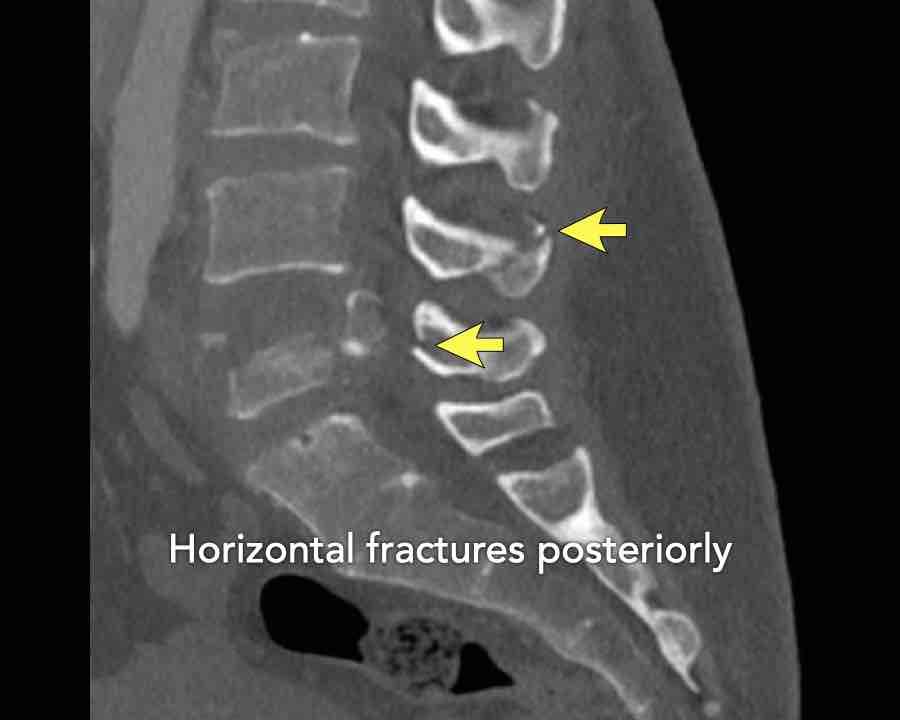

Continue with the next stack of images to classify level L2…

Scroll through images.

What is the highest AO-level?

Findings

- No dislocation ( no C type).

- Mainly horizontal fractures of spinous processus at multiple levels (B-type).

- Split fracture L2 (type A2).

Conclusion

Injury type B2 + A2 at level L2.